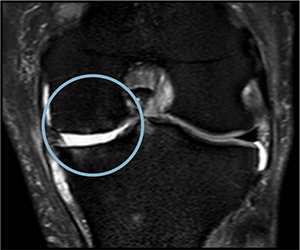

POST-TREATMENT

MAY 5, 2024